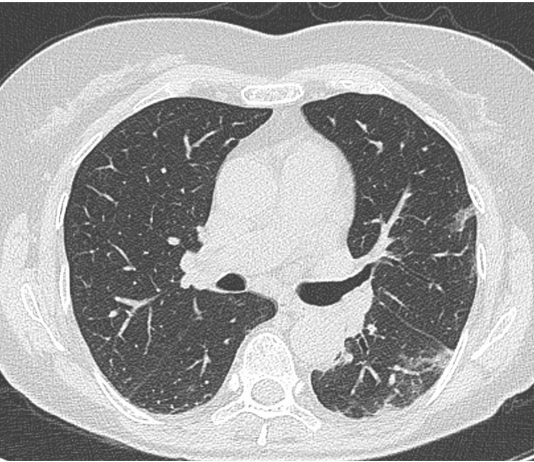

73-year-old male patient presented to the ED with fever for 10 days, not responding to paracetamol.

Chest radiography: